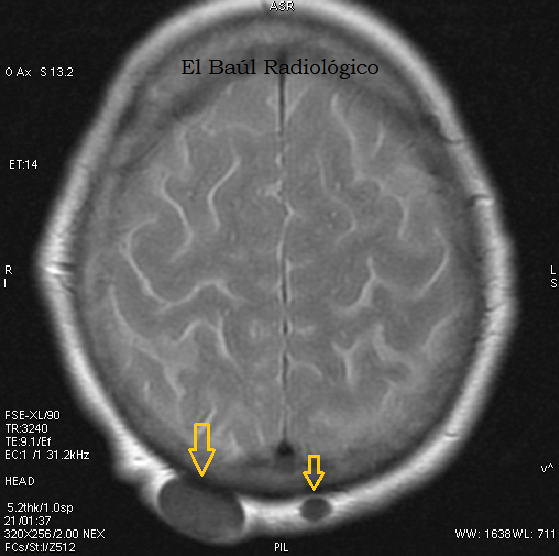

FIGURA 6) Los quistes sebáceos tambien se detectan en las exploraciones de TRM. Se presentan como un nódulo hipodenso, bien delimitado, que no tiene relación con el cráneo.

(Sebaceous cystsare detectedalsoin the explorations ofMRI.They appear ashypodense, well-defined nodes, which has no relation to the skull).

FIGURA 7) Por su elevada concentración en sales cálcicas, los quistes sebáceos no varían en las imágenes potenciadas en T2 (FLAIR-T2).

(Due toits high concentration ofcalcium salts theydo not changeinT2-weightedimages(FLAIR-T2).